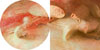

Íàòþðìîðò

Õëåá è ñîëü.